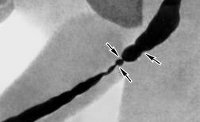

N35 Стриктура уретры